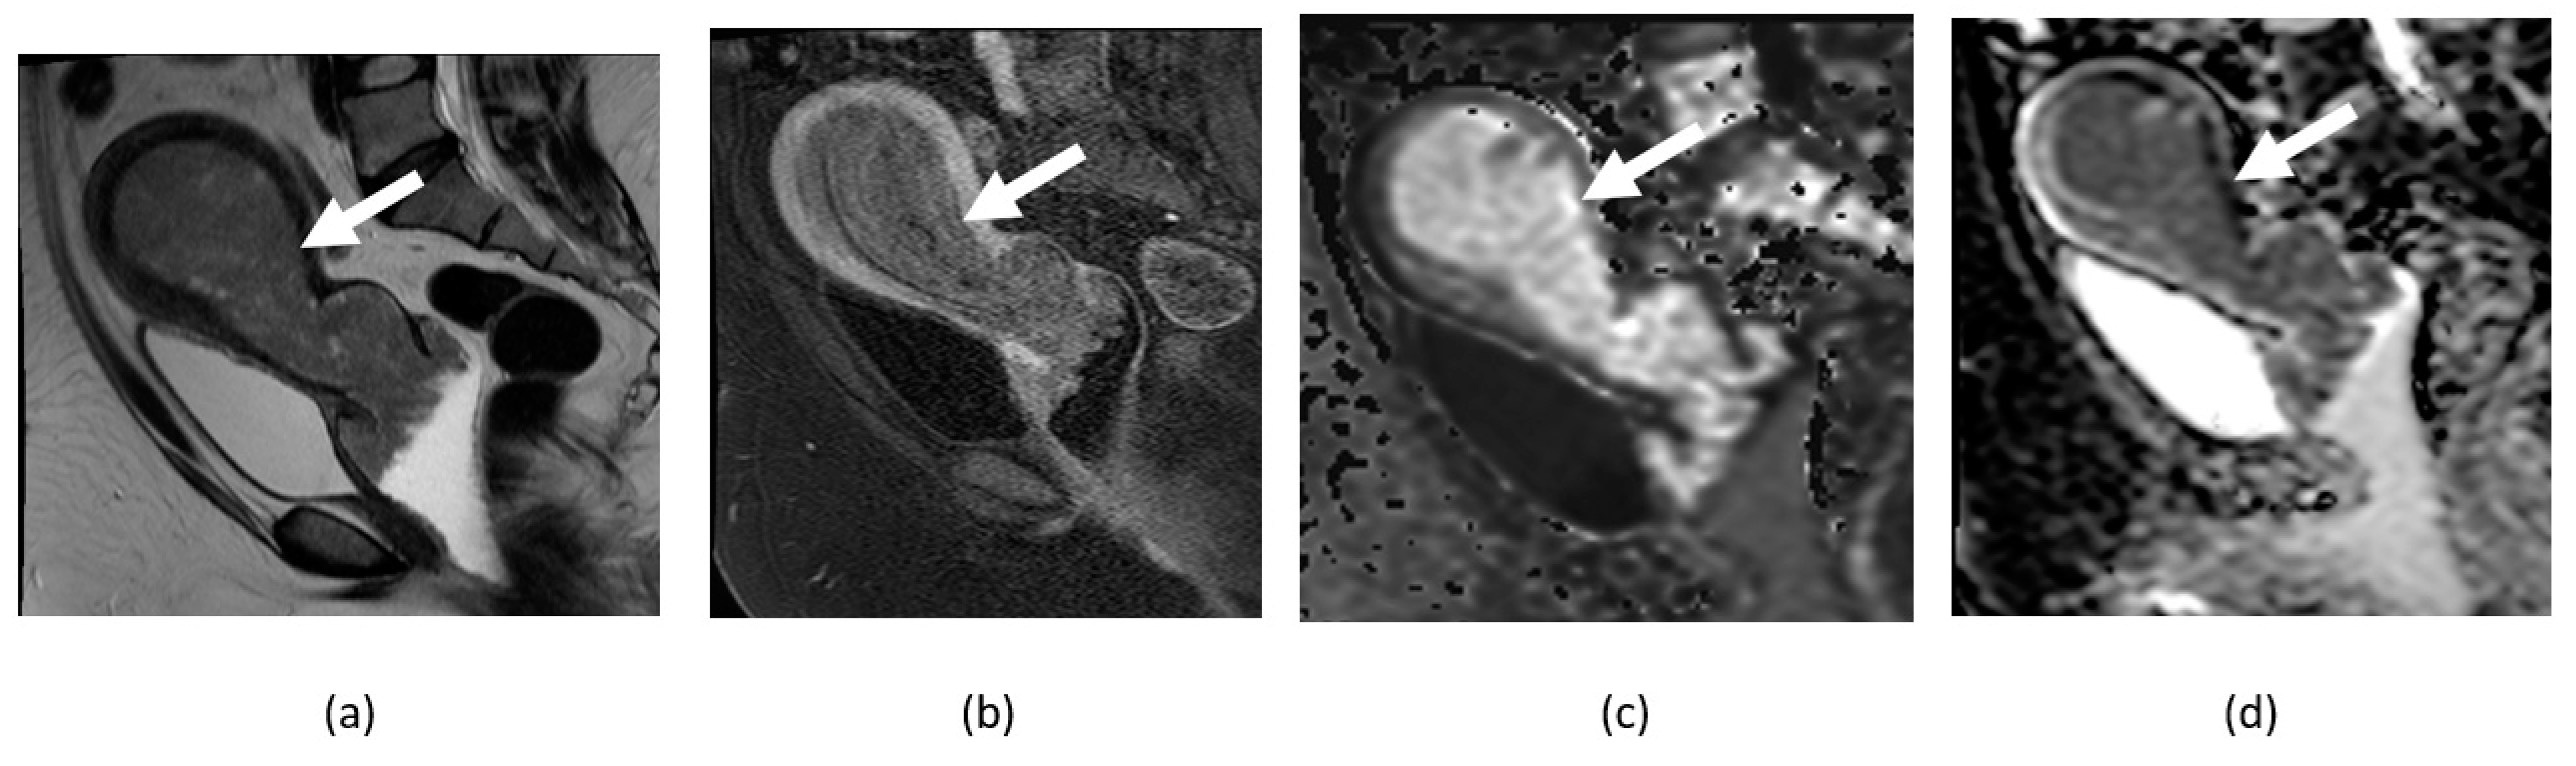

4.3. Ovarian Cancer